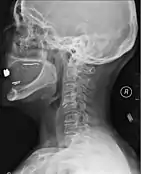

Diagnosis

A person's presentation in context of trauma or non-traumatic background determines suspicion for a spinal cord injury. The features are namely paralysis, sensory loss, or both at any level. Other symptoms may include incontinence.[89]

A radiographic evaluation using an X-ray, CT scan, or MRI can determine if there is damage to the spinal column and where it is located.[9] X-rays are commonly available[88] and can detect instability or misalignment of the spinal column, but do not give very detailed images and can miss injuries to the spinal cord or displacement of ligaments or disks that do not have accompanying spinal column damage.[9] Thus when X-ray findings are normal but SCI is still suspected due to pain or SCI symptoms, CT or MRI scans are used.[88] CT gives greater detail than X-rays, but exposes the patient to more radiation,[90] and it still does not give images of the spinal cord or ligaments; MRI shows body structures in the greatest detail.[9] Thus it is the standard for anyone who has neurological deficits found in SCI or is thought to have an unstable spinal column injury.[91]